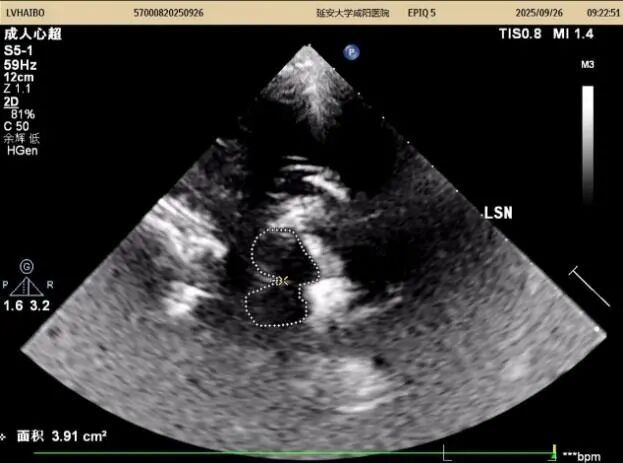

26日上午及下午14:00至15:50,以實(shí)際病例為媒介全流程質(zhì)控,從設(shè)備調(diào)試、探頭的選擇與放置、中腦(黑質(zhì)、紅核、導(dǎo)水管)、丘腦、第三腦室、豆?fàn)詈藚^(qū)域等的識(shí)別,到圖像優(yōu)化與測(cè)量規(guī)范,逐步演示標(biāo)準(zhǔn)操作流程,重點(diǎn)解析黑質(zhì)高回聲的識(shí)別與鑒別診斷。期間,結(jié)合患者病史,耐心答疑、細(xì)致指導(dǎo),引導(dǎo)醫(yī)師多維度理解技術(shù)要點(diǎn),提升實(shí)戰(zhàn)能力。同時(shí)對(duì)我科前期工作給予高度評(píng)價(jià)。

在專題授課環(huán)節(jié),張教授以《帕金森病的TCS與神經(jīng)調(diào)控專家共識(shí)-解讀與臨床應(yīng)用》為題,從帕金森病的發(fā)病率及早期診斷難點(diǎn)切入,以問題為導(dǎo)向,結(jié)合國(guó)內(nèi)外研究,系統(tǒng)講解了中腦黑質(zhì)超聲的設(shè)備要求、檢查體位、標(biāo)準(zhǔn)切面及關(guān)鍵核團(tuán)評(píng)估要點(diǎn),并通過典型圖像與病例,深入闡釋影像特征與臨床表現(xiàn)的關(guān)聯(lián)。針對(duì)實(shí)際工作中常見問題進(jìn)行了重點(diǎn)強(qiáng)調(diào),現(xiàn)場(chǎng)學(xué)術(shù)氣氛濃厚。王英莉主任總結(jié)指出,開展TCS需做到“準(zhǔn)、慢、細(xì)”—診斷精準(zhǔn)、隨訪耐心、觀察細(xì)致,并強(qiáng)調(diào)各亞專業(yè)組應(yīng)加強(qiáng)與臨床科室的縱深交流,融入科研思維。